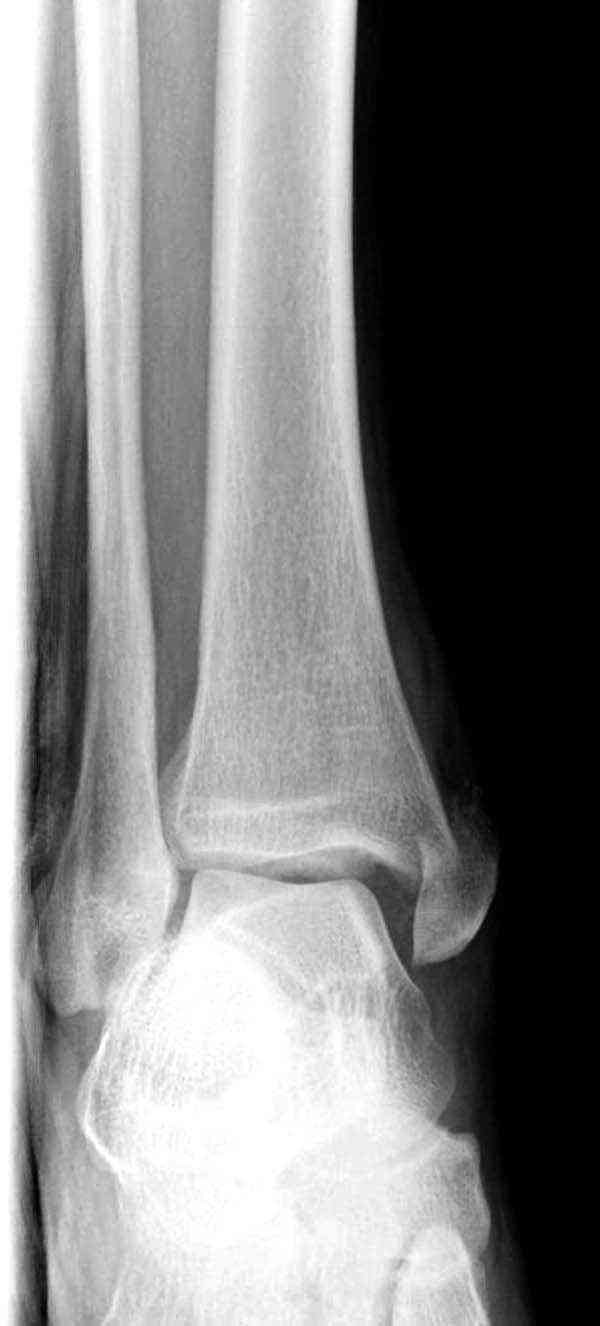

Случай прошлого года:пациентка-молодая ,крупная женщина ,30лет.Травма в начале апреля 2009г-пронационный перелом лодыжек с подвывихом стопы.Ко мне обратилась через 35 дней,прооперирована 22.05.2009г.Внутренняя лодыжка фиксирована по Веберу,наружная реконструктивной пластиной с наложением болта-стяжки.Иммобилизация "сапожок" в течении месяца,затем пригипсовано "стремя".Гипс снят 10.07.2009г

Достаточно быстрое восстановление функции.В октябре 2009г-почувствовала боль,в области рубца над гайкой открылся свищ.На Р-граммах-консолидация переломов и смещение гайки по стяжке.10.11.2009г-конструкции удалены,санация,заживление ран.В настоящее время пациентку ничего не беспокоит.На операции-раскручивание гайки-болталась на конце стяжки.Вопросы:какой механизм раскручивания и что я неправильно сделал?Свои версии:1)в области синдесмоза успела образоваться рубцовая ткань,которая при движении в суставе"пружинила",поскольку голеностопный сустав является спиральным, то и биомеханика подобна кривошипному механизму.2)Реконструктивная пластина не "реконструировалась" по форме лодыжки.Наложил,как есть.То есть подпружинивала сама пластина.Ну,это мои догадки.Что нужно,чтобы избегать впредь таких,пусть и не "страшных"осложнений:Рассверливать через лодыжку область синдесмоза?Ставить шайбу-гровер?Тщательно моделировать пластину?Прилагаю сравнительные снимки-сразу после операции и перед удалением конструкции.

Визуально никаких вопросов по репозиции не было.Да и на основании чего сомнения,что наружная лодыжка не полностью репонирована или прорезалась проволка ???Я не вижу...Снимок после репозиции справа.